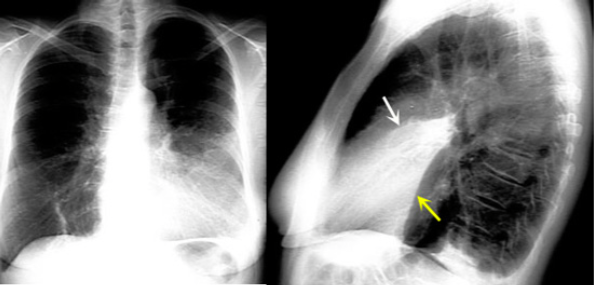

What is this consolidation?

Lingular Consolidation